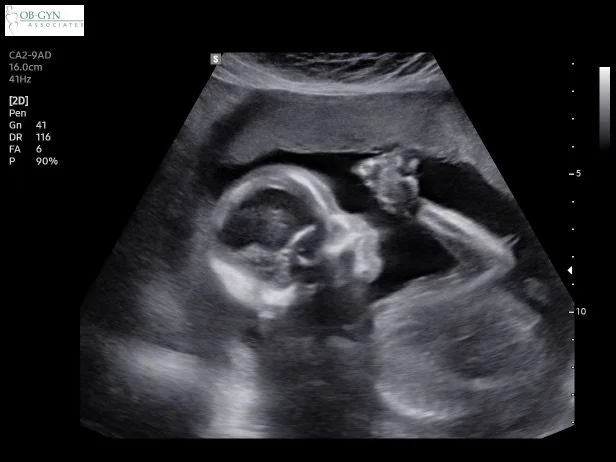

I had my first appointment a day before my birthday, and I was so nervous. I had to go by myself and I thought I would not be able to handle it if I had a miscarriage. But they did the ultrasound. I saw the baby and everything else was perfect! I was happy and relieved.

When I was 40 weeks + 2 days I had my last appointment. They did an ultrasound and said the baby was facing my left hip and probably very long. That day I went home and rested and went on a date to Food Truck Friday and drank a smoothie with dates.

First ultrasound

Anatomy scan